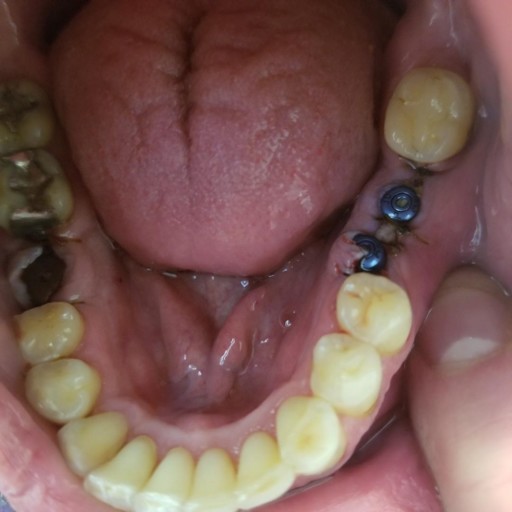

Implants

I had 3 implants done yesterday, with 2 that were next to each other (see picture). One is not aligned. I am also doing ortho care and went in today to have a new retainer fitted. The dentist said he did not want to do new impressions due to the...